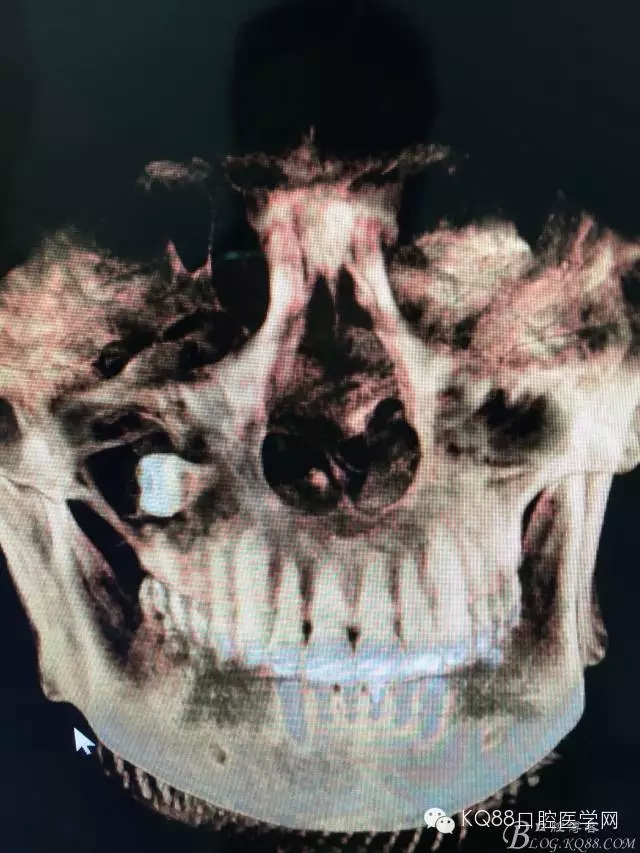

圖4.三維重建影像顯示:18牙體位于上頜竇內(nèi)。其上頜竇頰側骨壁破壞消失。左側骨壁完好無缺。